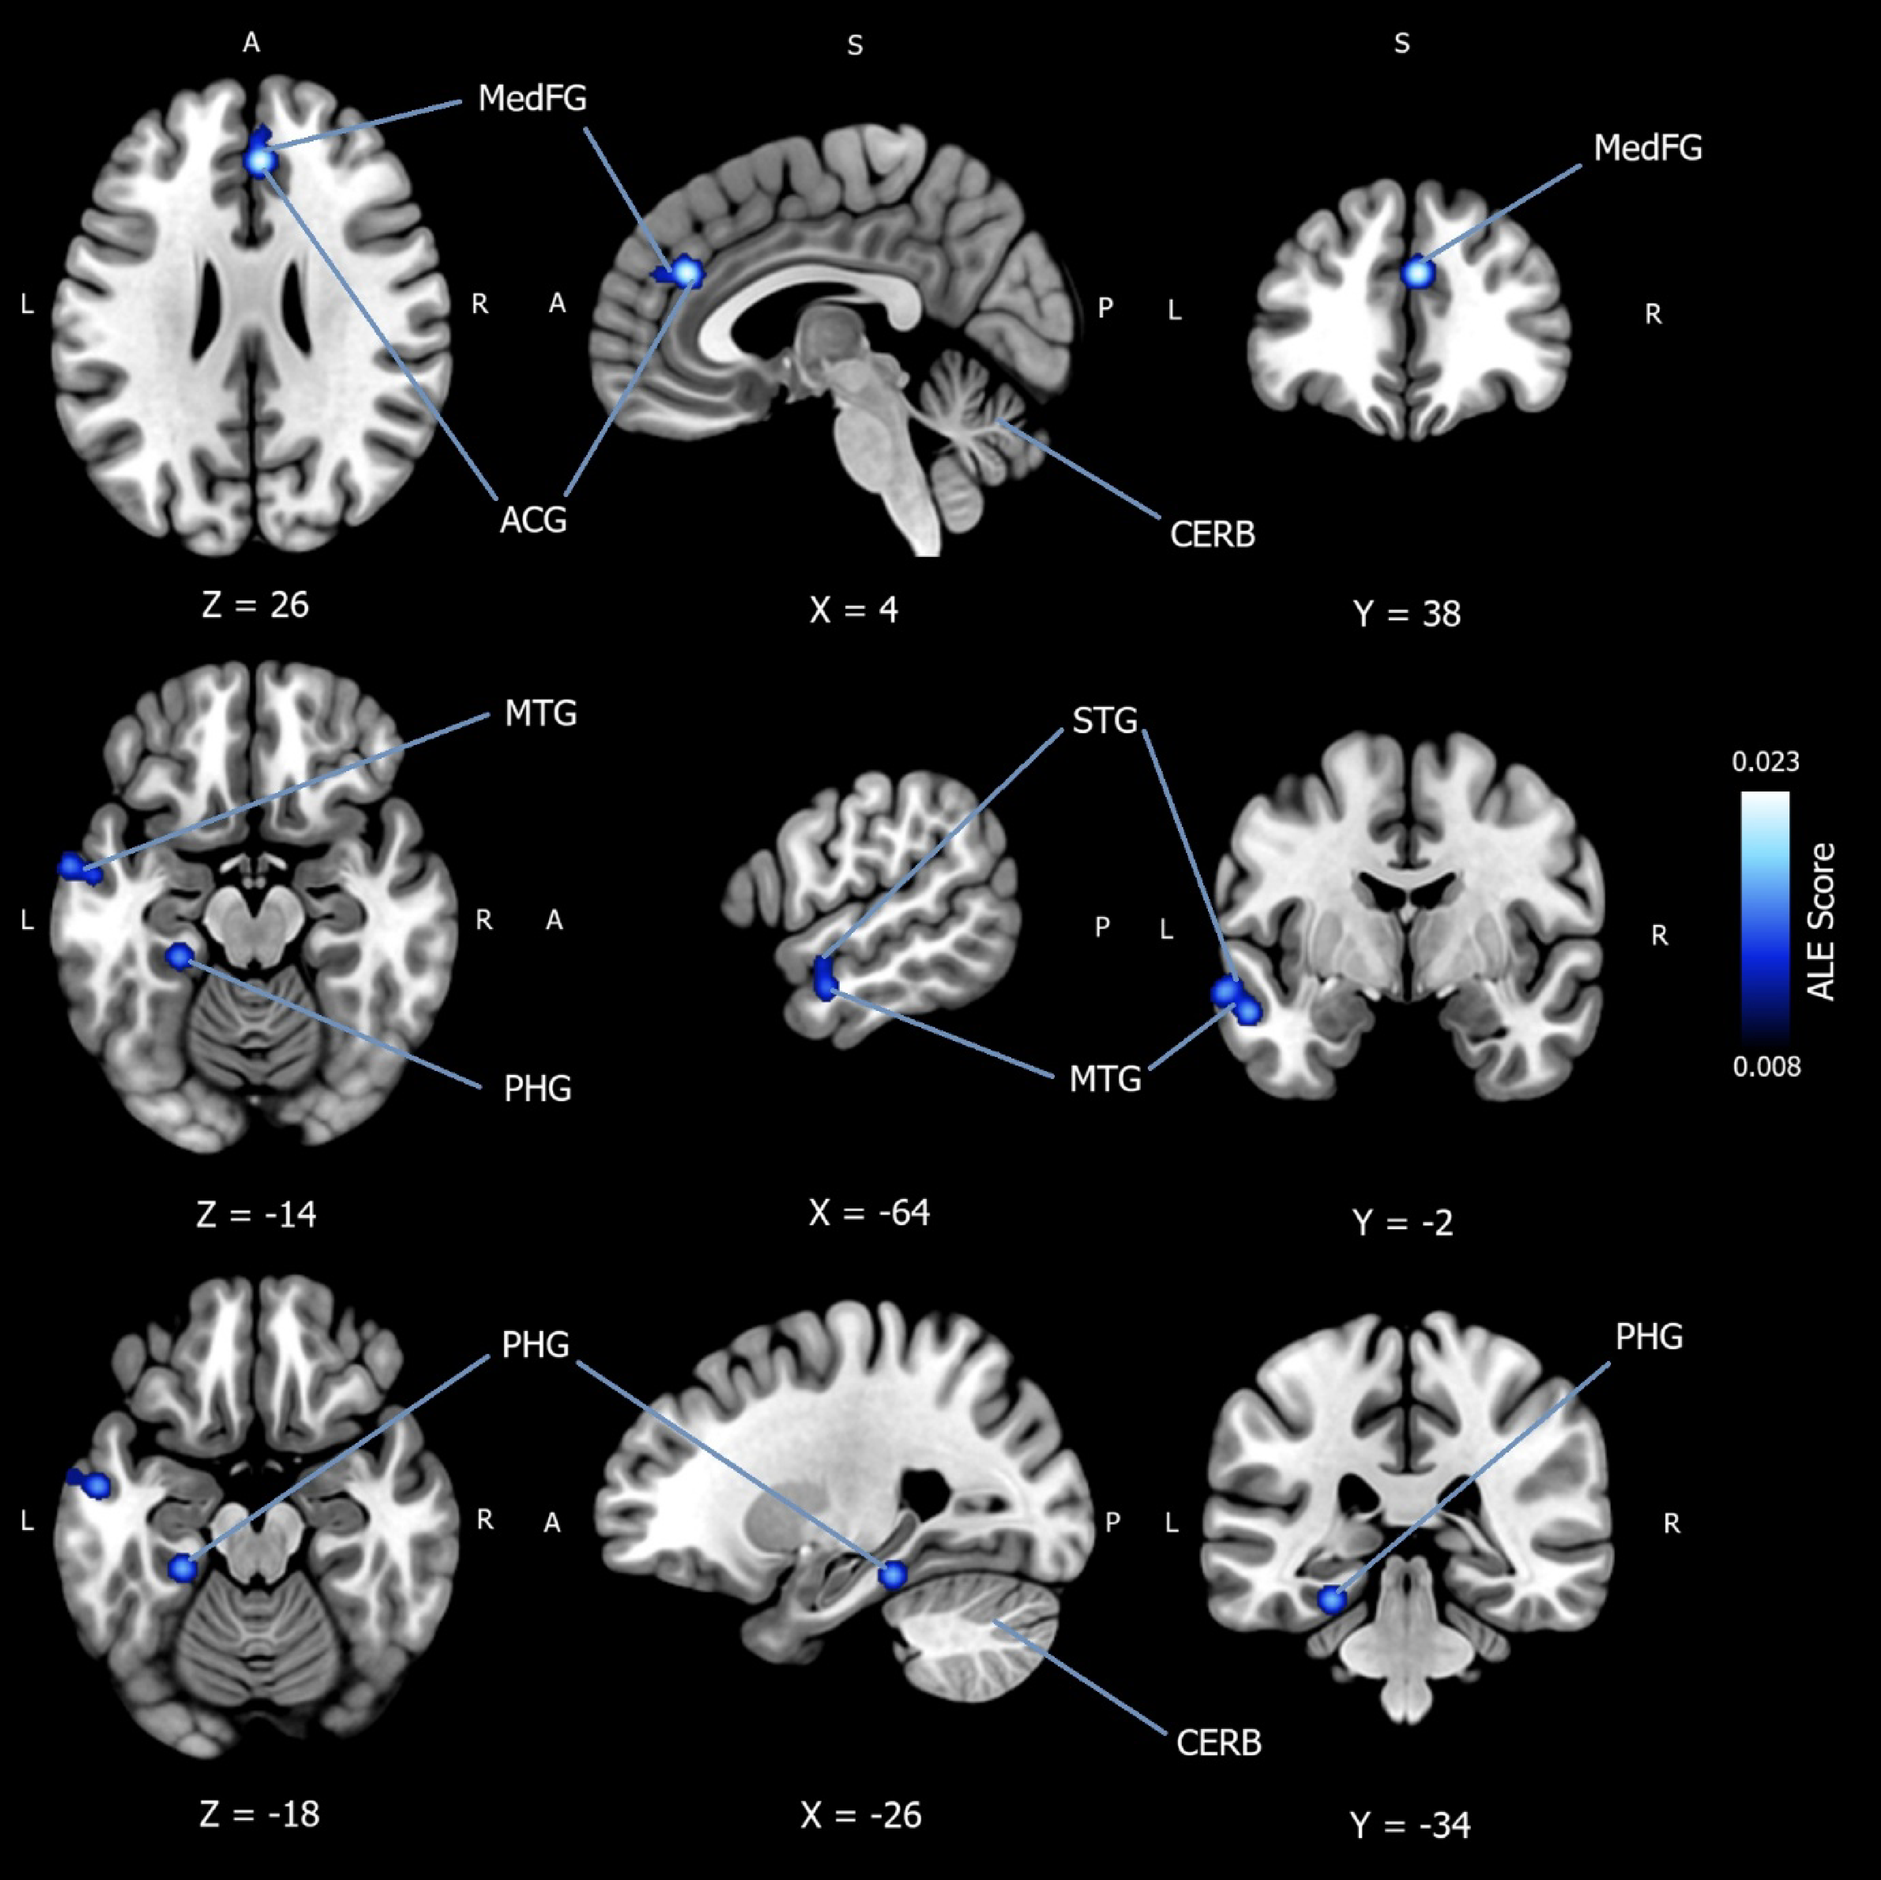

Fig. 3

Subgroup analysis for convergence of hypoactivation in mood disorder patients during implicit emotion regulation.Ā Activation likelihood estimation meta-analysis (nā= 225) showing convergence of hypoactivation in mood disorder patients compared to healthy controls (patients >ācontrols)Ā during implicit emotion regulation. Three cluster regions with five peak coordinates were identified using a cluster-level family-wise error correction threshold of p <Ā .05, with an uncorrected value of p <Ā .001. A rigorous threshold of 5,000 permutations was applied. The first cluster reported a peak coordinate (x =ā4, yā= 38, zā= 26) in the right and left medial frontal gyrus (BA9), extending over the anterior cingulate gyrus (BA32). The second cluster yielded two peak coordinates ([x = ā64, y = ā2, z = ā14] and [x = ā56, y = ā6, z = ā20]) in the left middle temporal gyrus (BA21), extending over the left superior temporal gyrus (BA22). Finally, two peak coordinates ([x = ā26, y = ā34, z = ā18] and [x = ā16, y = ā38, z = ā20]) were reported in the parahippocampal gyrus (BA36, BA35), spreading over the culmen. All locations were reported to be 100% grey matter. MedFGā= medial frontal gyrus; ACGā= anterior cingulate gyrus; MTGā= middle temporal gyrus; STGā= superior temporal gyrus; PHGā= parahippocampal gyrus; CERBā= cerebellum; ALE Scoreā= ALE value.